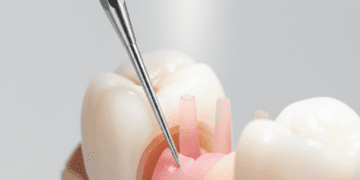

O diagnóstico é realizado por meio da anamnese, exame clínico e testes sensoriais. O dentista deverá analisar os sintomas descritos pelo paciente e avaliar a vitalidade da polpa com métodos que incluem:

- Teste de sensibilidade térmica: Aplicação de frio para verificar a resposta da polpa;

O tratamento visa eliminar a causa da irritação para permitir a recuperação da polpa. As principais condutas são:

- Remoção da cárie: Uma cavidade deve ser cuidadosamente preparada para remover tecido cariado;